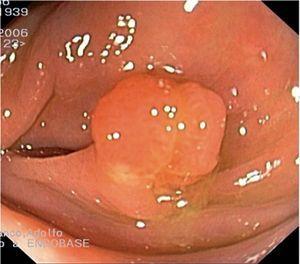

Fig. 3. Examples of flat lesions with conventional examination and after the application of indigo carmine 0.2-0.5%. a, b) Small flat adenoma, 3 mm in size. c, d) Large flat adenoma, 15 mm in size. e, f) Completely flat lesion (IIb in the Japanese classification). g, h) Depressed lesion, 3 mm in size) (IIc in the Japanese classification). I, J) Depressed lesion, 7 mm in size, histopathological study revealed submucosally invasive cancer (traditionally IIc in the Japanese classification, although recently such depressed lesions with a distinct central protrusion indicating submucosal invasion are termed IIc + Is). k, l) Flat elevated lesion with central depression, 10 mm in size, corresponding to a submucosally invasive cancer (IIa + IIc in the Japanese classification).